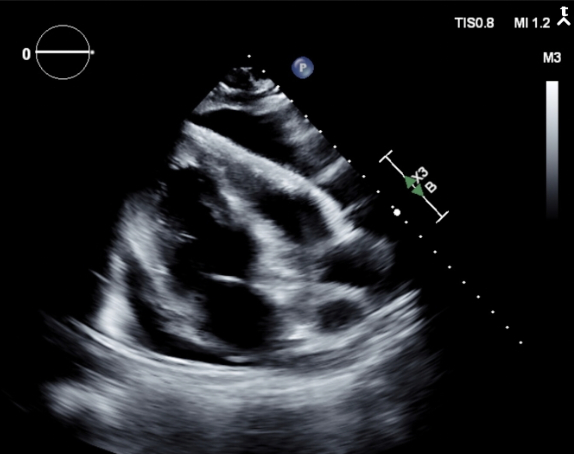

Abstract Body (Do not enter title and authors here): Primary mediastinal embryonal carcinoma is an exceptionally rare and aggressive extragonadal germ cell tumor, comprising less than 2% of mediastinal germ cell neoplasms. Cardiovascular complications, including pericardial effusion and tamponade physiology, are even more infrequent, with only isolated cases reported. We present the case of a 35-year-old male with no significant medical history who presented with progressive dyspnea, pleuritic chest pain, and right shoulder discomfort. Imaging revealed a massive anterior mediastinal mass (21.2 × 14.3 × 20.3 cm) compressing the left lung and shifting mediastinal structures rightward, with direct extension into the left atrium and pulmonary veins (Image 1 and 2). Echocardiography demonstrated a moderate-to-large pericardial effusion with right atrial inversion and respiratory variation in mitral inflow, suggestive of early tamponade (Image 3). However, due to stable hemodynamics and significant distortion of normal anatomy from the tumor mass, pericardiocentesis was deferred as high-risk. Multidisciplinary teams opted for conservative management, and the patient was initiated on systemic chemotherapy with ifosfamide, etoposide, and cisplatin. Serial imaging demonstrated stabilization of the pericardial effusion and early signs of tumor response. Pathology confirmed embryonal carcinoma with elevated tumor markers (AFP 514 ng/mL, β-hCG 158 mIU/mL, LDH 3,078 U/L). Neurological evaluation for multifocal infarcts revealed a brain metastasis and suspected embolic phenomena; vascular imaging showed a left popliteal artery thrombus. The case illustrates a rare instance where both malignant pericardial effusion and external tumor compression contributed to tamponade physiology without overt clinical collapse. It highlights the complexity of managing cardiac involvement in malignancy, where anatomy, mass effect, and clinical stability guide intervention. This case reinforces the need for individualized cardiovascular decision-making and interdisciplinary coordination in rare oncologic presentations involving pericardial pathology.